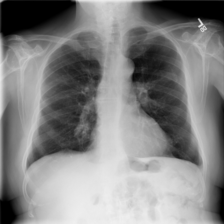

While these resources enable large-scale model development and benchmarking, they are also known to exhibit critical challenges that complicate clinical translation. The most notable problems are imperfect labels derived from automated text mining approaches [16, 17], demographic and institutional biases that induce domain shift [18, 19, 20], and evaluation protocols that do not reliably reflect clinical operating points [21, 22]. Collectively, these factors can produce deceptively high internal performance that does not persist under external validation [23]. Automated report mining has enabled dataset curation at scale for datasets such as CheXpert, MIMIC-CXR, ChestX-ray14, and PadChest, but remains vulnerable to negation, uncertainty, and study-level misalignment, leading to false positives/negatives and label drift across conditions and sites [24]. Such noise is sufficient for training, yet it constrains model reliability when radiologist consensus is the standard. An example case of automated labelling leading to a false positive for Pneumonia is shown in Figure 1. Most large public datasets originate from single centres or health systems and differ in populations, acquisition hardware, protocols, and preprocessing. Models can therefore exploit site-specific artefacts (e.g., devices, overlays, or processing fingerprints) rather than pathologies, yielding performance that collapses when scanners or workflows change [25, 26]. While AUROC and related metrics are useful and widely adopted for ranking classifiers, they obscure clinically meaningful operating points and the asymmetric costs of false positives versus false negatives [21, 22]. Under class imbalance, AUPRC and threshold-dependent metrics (Sensitivity, Specificity, F1) are more informative [27], but only when decision thresholds are specified and validated appropriately. In this study, we make the following contributions:

Refer to caption

Figure 1: Example radiography report from the MIMIC-CXR dataset. The associated chest radiograph is labelled as Lung Cancer and Pneumonia by the automated CheXpert labeller. Pneumonia indicators (red) are negative mentions, leading to a false diagnosis.